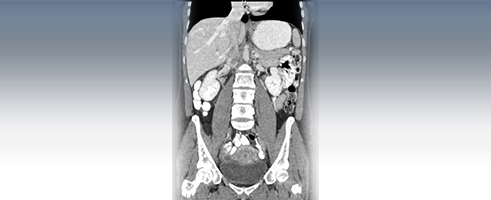

A CT scan is a diagnostic test that takes cross sectional pictures of the patient's internal anatomy. A CT scan creates highly detailed, cross sectional images of body parts and internal organs. CT can show bone and soft tissue structures such as internal organs, muscles, and blood vessels. It can be utilized to detect and diagnose a wide variety of medical conditions and abnormalities of nearly any body organ. A CT scan may require a contrast media such as barium or IV contrast to better highlight abnormalities. These examinations are performed by certified technologists, and every examination is directly supervised and interpreted by board certified radiologists.

A CT scan is made up of a series of x-rays which are processed by a computer to produce cross-sectional pictures of the body. These cross-sectional images allow one to look at the inside of the body.

CT Studies Offered:

- Abdomen